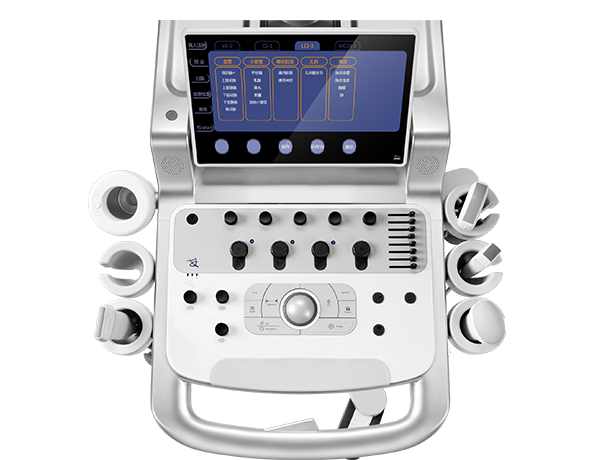

科学操作面板 精简设计

电动升降可旋转操控面板

电动升降可旋转操控面板 简约界面 科学布局

简约界面 科学布局 -